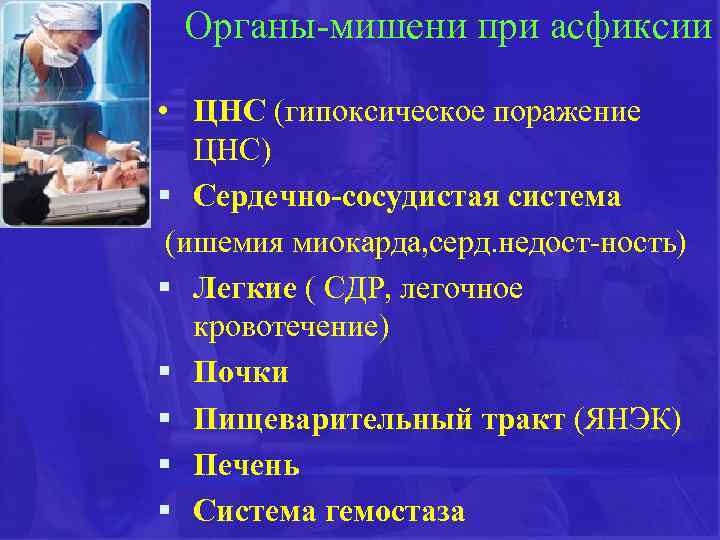

Органы-мишени при асфиксии • ЦНС (гипоксическое поражение ЦНС) § Сердечно-сосудистая система (ишемия миокарда, серд. недост-ность) § Легкие ( СДР, легочное кровотечение) § Почки § Пищеварительный тракт (ЯНЭК) § Печень § Система гемостаза

Органы-мишени при асфиксии • ЦНС (гипоксическое поражение ЦНС) § Сердечно-сосудистая система (ишемия миокарда, серд. недост-ность) § Легкие ( СДР, легочное кровотечение) § Почки § Пищеварительный тракт (ЯНЭК) § Печень § Система гемостаза